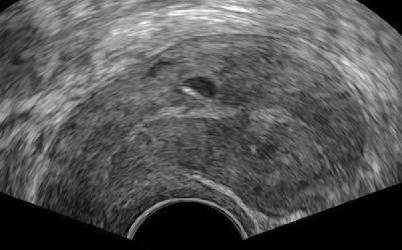

Abb. 1

Die asymmetrische Verdickung, meist der Hinterwand des Uterus, ist ein charakteristisches Kennzeichen der Adenomyose. In diesem Fall ist die Hinterwand dreimal so dick wie die Vorderwand